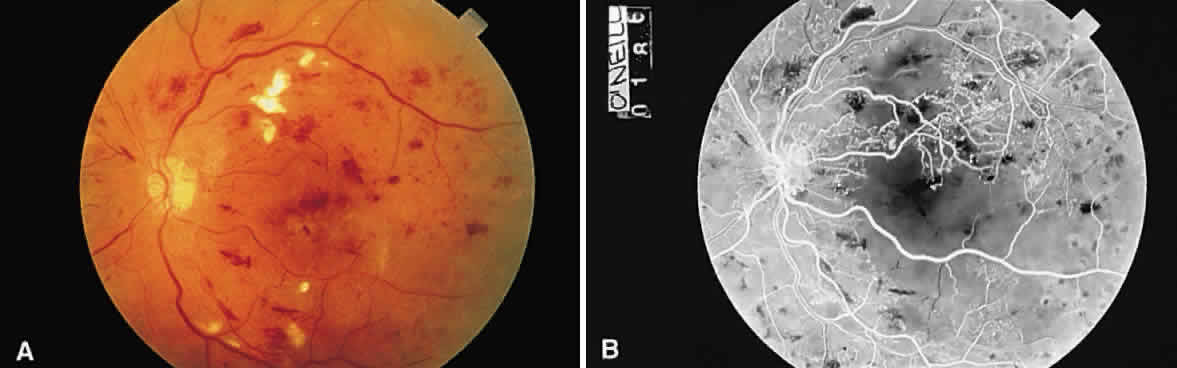

Cotton-wool spots are observed mainly in the posterior pole of the retina (Fig.23) The reason for this geographic restriction is not clear. Occlusion of the most superficial radially oriented peripapillary capillaries (confined in distribution to the posterior pole) has been implicated in the pathogenesis of cotton-wool spots.9 It is also possible that nerve fiber infarcts in the periphery are not visualized because there is insufficient inspissated axoplasmic material in this location.

Fig. 23. Multiple cotton-wool spots along with retinal hemorrhages in a superior temporal branch retinal vein occlusion.